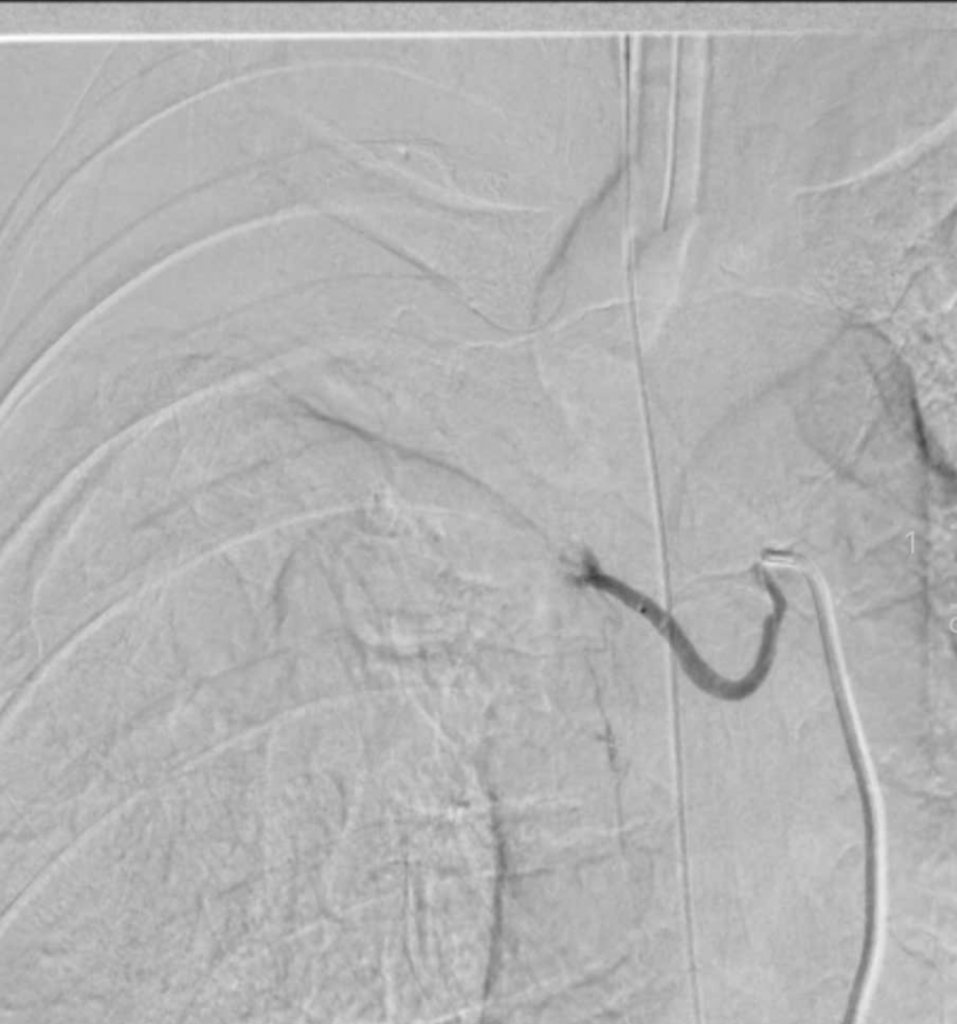

Quá trình can thiệp tắc động mạch phế quản

BS.CKI. Trịnh Đình Hiếu – Đơn vị Can Thiệp Mạch Bệnh viện Đa khoa Xuyên Á, người trực tiếp thực hiện thủ thuật cho biết: “Trong quá trình can thiệp, các bác sĩ Đơn vị Can Thiệp Mạch đã phối hợp cùng các bác sĩ khoa Gây Mê Hồi Sức và khoa Hồi Sức Tích Cực để ổn định tình trạng huyết động của bệnh nhân. Qua đường ống nhỏ luồn từ động mạch đùi, các bác sĩ Đơn vị Can Thiệp Mạch đã đưa dụng cụ chuyên dụng đến tận nhánh động mạch phế quản bị tổn thương và tiến hành tắc mạch máu tổn thương bằng chất tắc mạch, kiểm soát được nguồn máu chảy và giảm nguy cơ ho ra máu tái phát về sau.”

Hình ảnh trước can thiệp